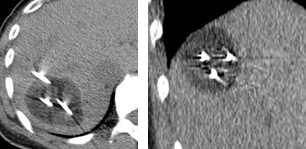

肝悪性腫瘍に対する経皮的な低侵襲治療には、ラジオ波、マイクロ波、レーザー治療など熱凝固を用いて治療する方法があります。経皮的凍結治療は腫瘍組織を凍結することにより壊死させる治療法で、近年小径腎悪性腫瘍に対して保険診療が承認されました。経皮的な針で凍結を得る方法は、高圧のアルゴンガスを針内に送り込み、針の先端部に内装された二重構造の熱交換器部分でのJoule-Thomson効果により低温を得るもので、針の熱交換器部分は-185℃まで冷却されます。凍結治療はラジオ波治療などと比べて、①細胞死が細胞自体の機械的な破壊であるため変性蛋白が生成されない、②凍結による麻酔効果により凍結中の痛みがない、③MRIやCTにより凍結範囲を画像的にモニタリングすることができる、などの利点を有しています。

海外では肝悪性腫瘍に対しても凍結治療は実施されており、良好な治療成績が報告されています。本邦においても肝悪性腫瘍に対する経皮的凍結治療を安全に実施できるようになることを目指し本研究は計画されました。

転移性骨軟部腫瘍や類骨骨腫などの有痛性骨軟部腫瘍に対する治療には、1)腫瘍を切除する方法,2)鎮痛剤を内服する方法,3)放射線照射による治療,4)専用針を刺してラジオ波で凝固・焼灼する治療, 5)動脈・静脈から薬剤(悪性の場合は抗がん剤を含む)を投与する方法、などがありますが、それぞれの治療に一長一短があります。経皮的凍結治療は腫瘍組織を凍結することにより壊死させる治療法で、近年小径腎悪性腫瘍に対して保険診療が承認されました。経皮的な針で凍結を得る方法は、高圧のアルゴンガスを針内に送り込み、針の先端部に内装された二重構造の熱交換器部分でのJoule-Thomson効果により低温を得るもので、針の熱交換器部分は-185℃まで冷却されます。凍結治療はラジオ波治療などと比べて、①細胞死が細胞自体の機械的な破壊であるため変性蛋白が生成されない、②凍結による麻酔効果により凍結中の痛みがない、③MRIやCTにより凍結範囲を画像的にモニタリングすることができる、などの利点を有しています。

海外では有痛性骨軟部腫瘍に対しても凍結治療は実施されており、良好な治療成績が報告されています。本邦においても有痛性骨軟部腫瘍に対する経皮的凍結治療を安全に実施できるようになることを目指し本研究は計画されました。

肺腫瘍や骨軟部腫瘍に対するラジオ波治療は我が国では保険診療が承認されていません。しかし、欧米からは手術と比べて低侵襲なラジオ波治療の報告が数多くなされています。本研究では、転移性肺癌、疼痛を伴う骨腫瘍(転移性骨腫瘍、類骨骨腫など)を中心に、CTによる画像誘導下にラジオ波治療を行い、その安全性と有効性を評価しています。